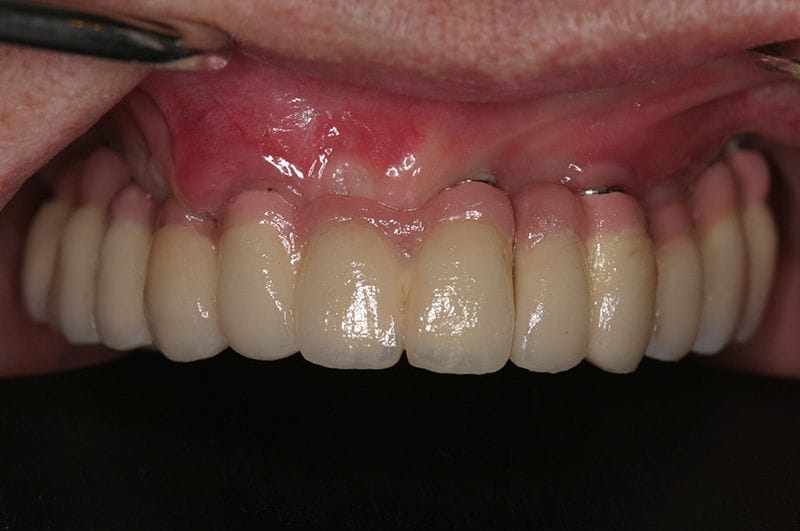

術後照片